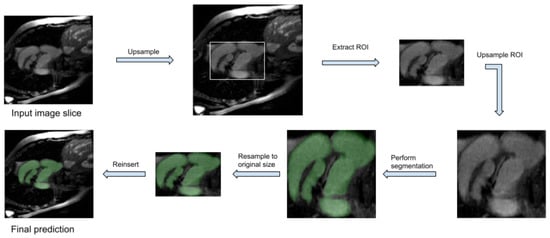

We have first explored the theoretical benefit of a perfectly selected ROI. In this context, image slices are first upsampled bilinearly to , a bounding box of the labelled area is computed using the ground truth mask and the area delimited by this box is cropped, resized to , and then fed to the model. At the time of evaluation, the ROI was reinserted into the original image slice, resized to its original dimensions. Thus, the 3D volume is processed slice by slice, with the model itself processing only the ROI of each slice. The procedure is depicted in Figure 1.

Figure 1.

The flow-diagram that supports our approach. Before the training process starts, two scaling steps and a cropping step are performed: each original image slice is resized to and, from this enlarged image, a ROI is cropped (by using the corresponding ground-truth) and resized to . The segmentation model is trained on these processed images and a set of masks are predicted for each input. Finally, the masks are re-scaled to the original dimensions and re-inserted in the original image.

Essentially, the steps are exactly the same as depicted in Figure 1, but instead of using the ground truth mask to compute the ROI box coordinates, the segmentation mask predicted by the Standard model is used.